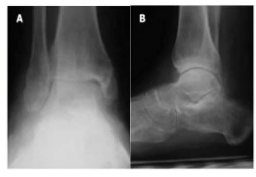

Open ankle fracture in a diabetic performed with minimal to no incision using a external fixation device along with regenerative medical therapy.

Many diabetic patients have ankle fractures. These can be extremely debilitating to the individual. Use of internal hardware can cause detrimental problems to these individuals. They may develop severe infection and/or Charcot foot deformity. At the Comprehensive Foot and Ankle Institute, we specialize in minimal incision surgery for diabetic and open ankle fractures along with regenerative medical therapy, and you can review Dr. Singh’s background and training for these complex cases here.

Note that the patient has a severe open ankle fracture. The x-ray on the left A, B and C show the leg bone in the tibia and the fibula completely exposed to the air with the foot bones 90 degrees to the leg. The only thing that is holding the patient’s leg is soft tissue. This is a medical and surgical emergency. Because this is a open ankle fracture there is a high probability of having osteomyelitis. There is also a high probability of a below the knee amputation.